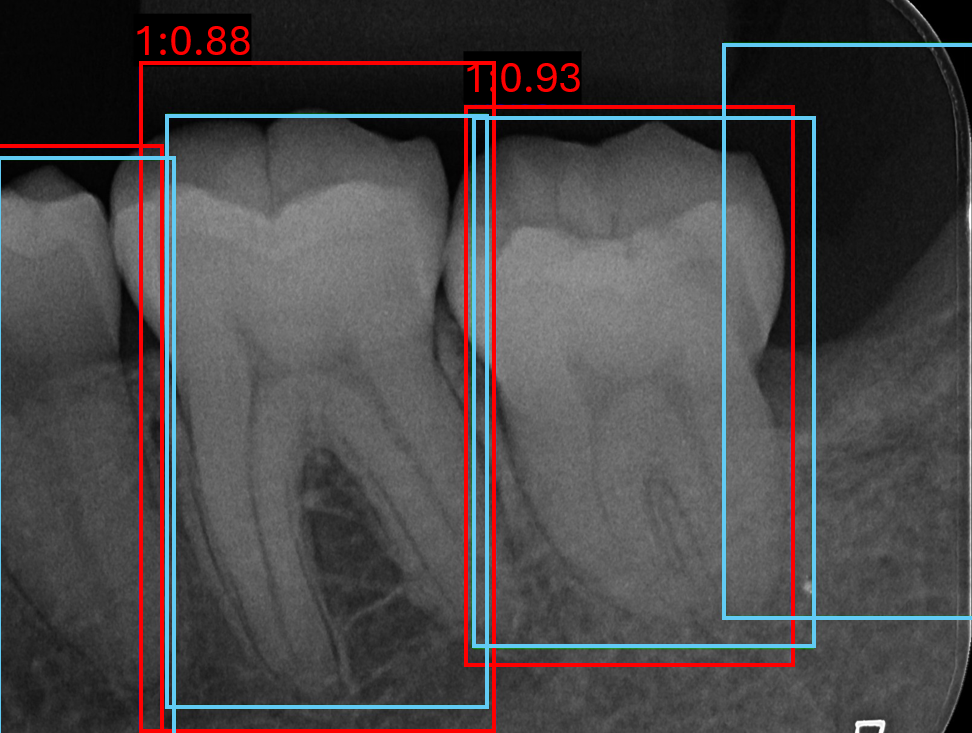

Figure 7 shows qualitative examples of detection performance on the validation set. Both models generally localise tooth boundaries with high precision, although analysing RTMDet performance indicates occasionally grouping of multiple teeth within a single bounding box, while still often retaining the appropriate number of boxes per tooth in the image. In some cases, both methods detect teeth absent from the annotations, suggesting improved actual sensitivity relative to the ground truth but at the cost of reduced quantitative precision.

Refer to caption

(a) Image 119 YOLOv8

(b) Image 120 YOLOv8

(c) Image 171 YOLOv8

(d) Image 119 RTMDet

(e) Image 120 RTMDet

(f) Image 171 RTMDet

Figure 7: Six validation images with overlaid bounding box results, where light blue is the target boxes and red is the predicted boxes.

Both models consistently fail on PLS classes, despite its higher sample size compared to ARR and triple root classes, shown in Figure 7(b) and Figure 7(e). This limitation is likely due to the visual similarity between healthy and widened PLS cases, indicative of a more challenging detection problem. In contrast, ARR and triple root teeth exhibit richer and more distinctive features, leading to stronger performance overall. However, false negative predictions for ARR remain evident throughout, in Figure 7(c) and Figure 7(f).